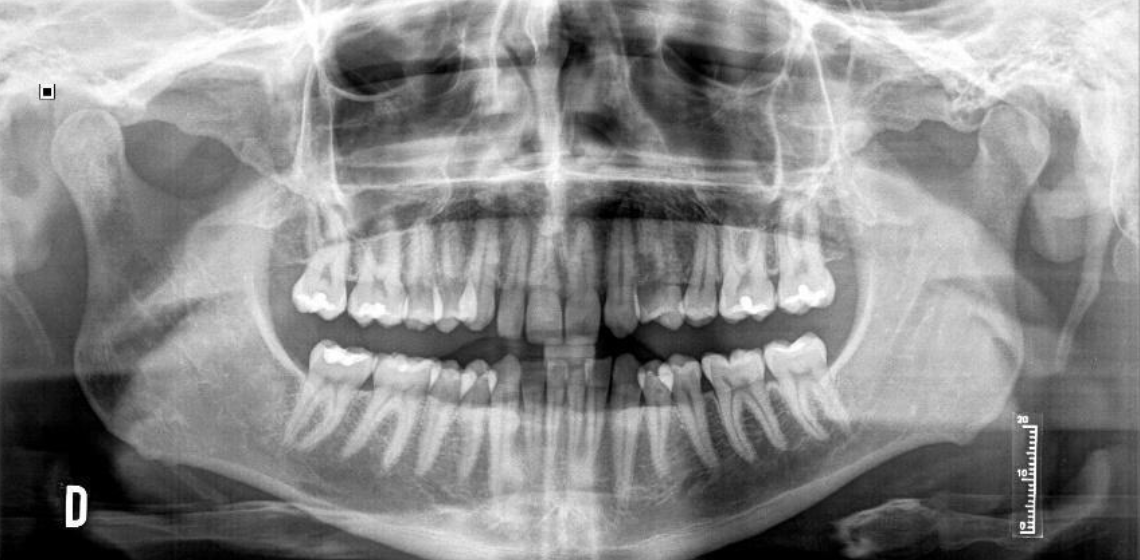

Retratamiento multidisciplinar de una agenesia de un incisivo lateral superior con un implante cerámico monobloque. A propósito de un caso clínico